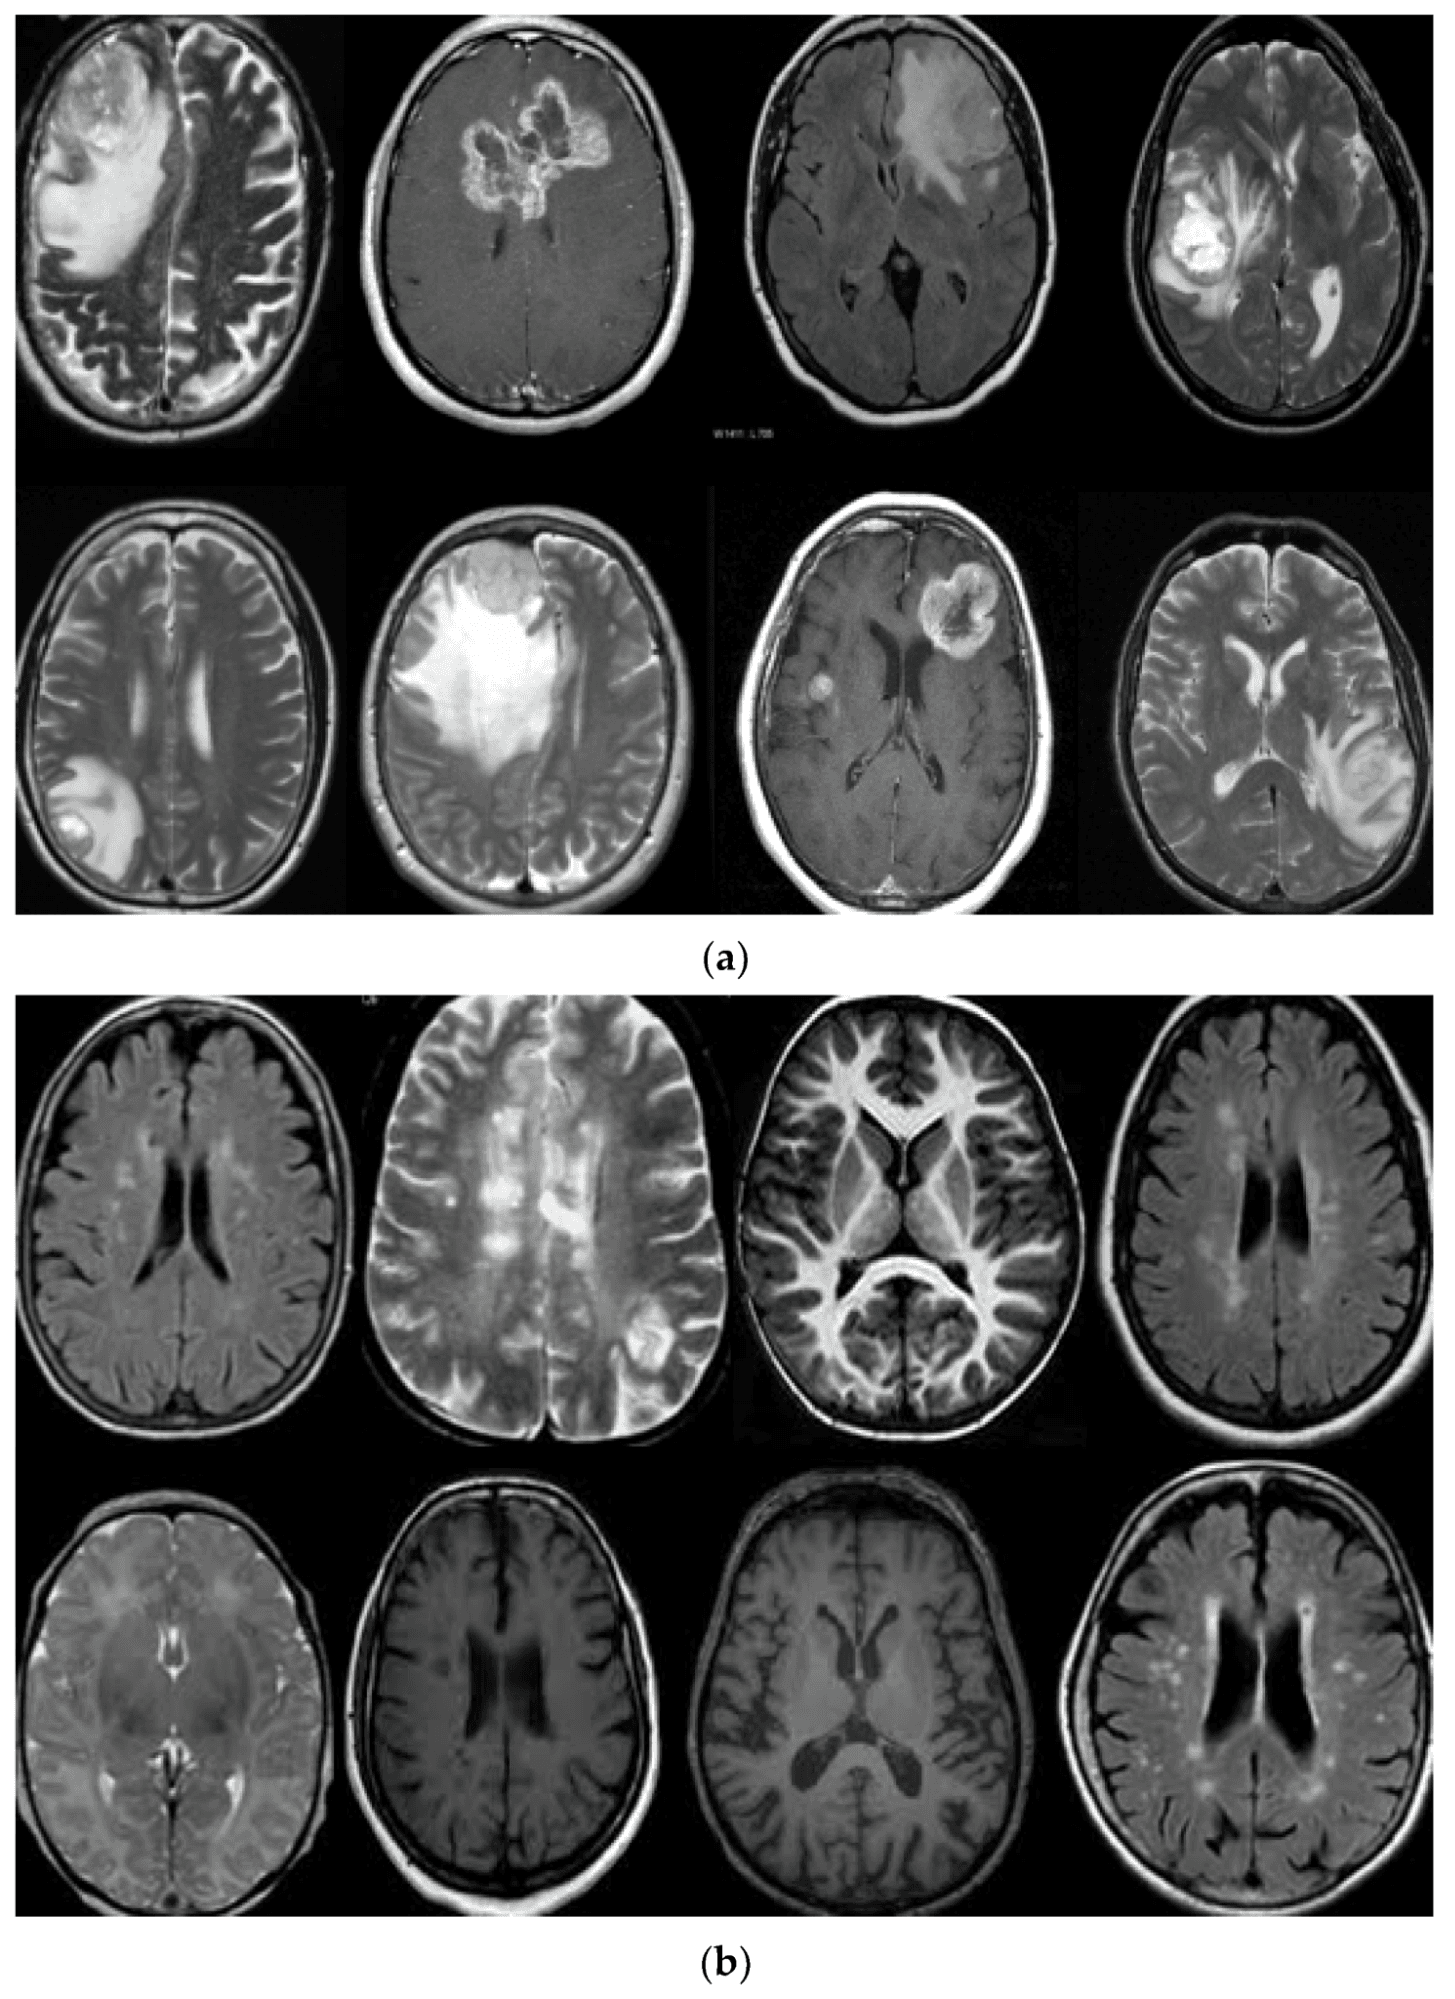

- يتضمن تحليل الصور الطبية مثل الأشعة السينية والرنين المغناطيسي والأشعة المقطعية

- تشخيص الأمراض والحالات الطبية بسرعة ودقة، مثل السرطان والالتهاب الرئوي وأمراض القلب

- تشخيص أكثر دقة، والكشف المبكر عن الأمراض، وتحسين نتائج المرضى.